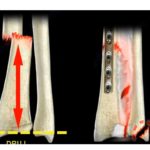

Fracture Of The Capitellum

Courtesy: Prof Nabil Ebraheim, University of Toledo, Ohio, USA